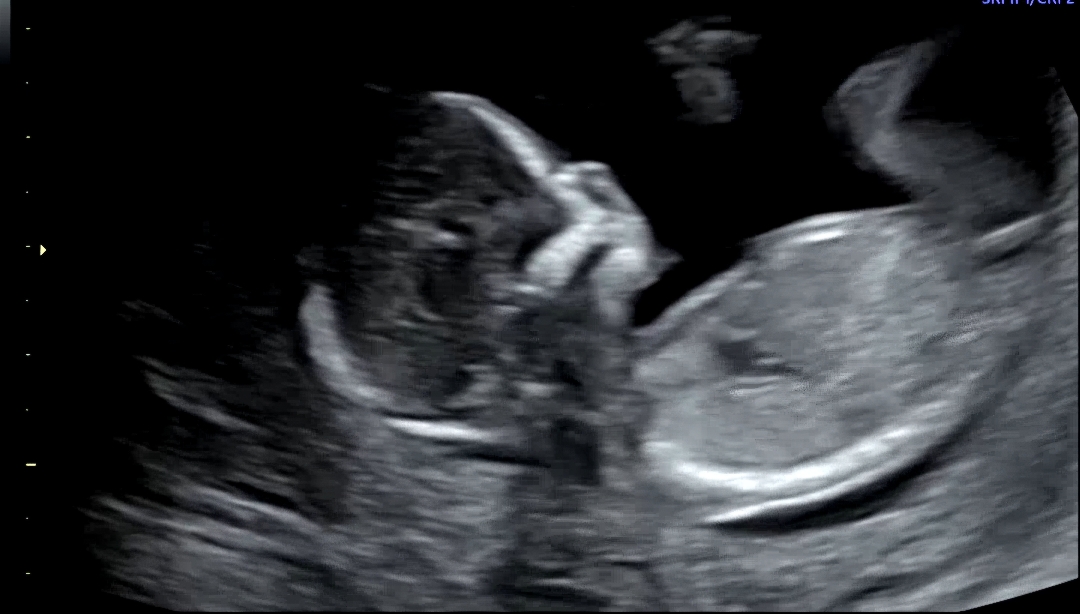

13주차에요 동영상캡쳐했는데 알 수 있을까요?

딸같네요